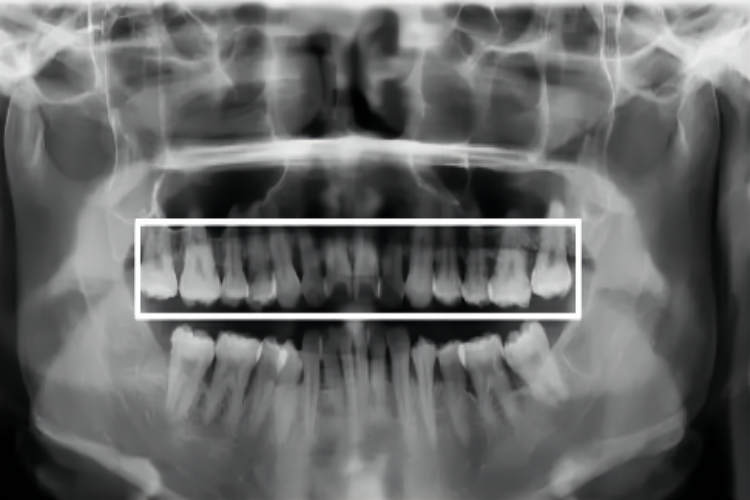

牙槽骨水平吸收指牙槽间隔、唇颊侧或舌侧的嵴顶边缘呈水平吸收,垂直吸收指牙槽骨发生垂直方向或斜形吸收,与炎症、创伤相关。

水平型吸收:水平型吸收是牙槽骨是常见的吸收方式,牙槽间隔、唇颊侧或舌侧的嵴顶边缘呈水平吸收。吸收初期表现为牙槽嵴顶的硬骨板消失,或嵴顶模糊呈虫噬状。嵴顶的少量吸收使前牙的牙槽间隔由尖变平或凹陷,在后牙则使嵴顶由宽平变凹陷,以后牙槽骨降低,形成骨上袋。

垂直型吸收:垂直也称角型吸收,指牙槽骨发生垂直方向或斜形吸收,与牙根面之间形成一定角度的骨缺损,牙槽嵴的高度降低不多,牙根周围的骨吸收较多。垂直骨吸收大多形成骨下袋,牙周袋底位于骨嵴的根方。